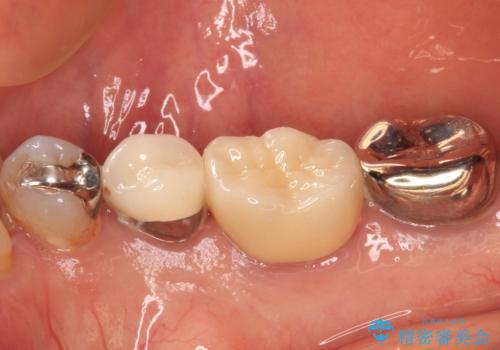

銀歯を外したところ、非常に大きなむし歯が認められましたが、神経組織には及んでおらず、速やかにオールセラミッククラウンによる補綴治療を行いました。